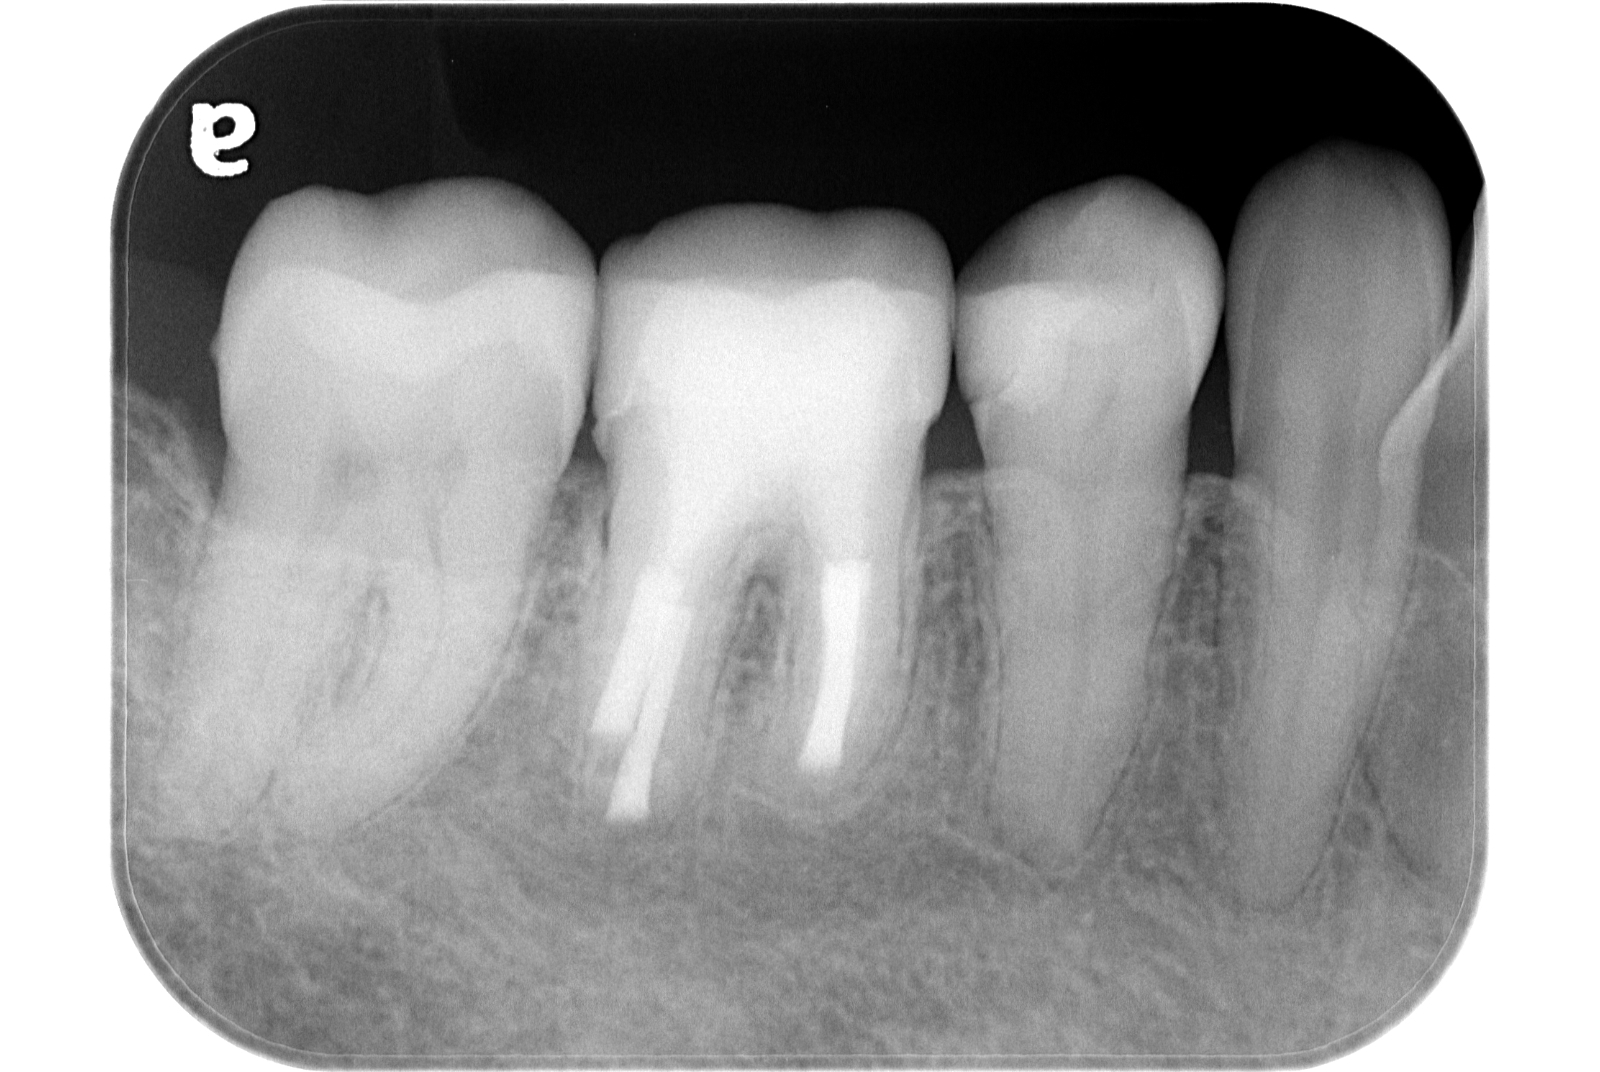

治療例 写真とレントゲン

治療前

治療後

※治療例に記載の情報はあくまでも症例に対してのものとなります。

| 費用 | 隔壁 11,000円(税込) |

|---|---|

| 初回根管治療 大臼歯 143,000円(税込) | |

| 支台築造 レジンコア 11,000円(税込) | |

| 治療期間 | 1週間 |

| 治療回数 | 2回 |

| 主な副作用とリスク | 根管治療が奏功しなかった場合、外科的歯内療法へ移行します。 |